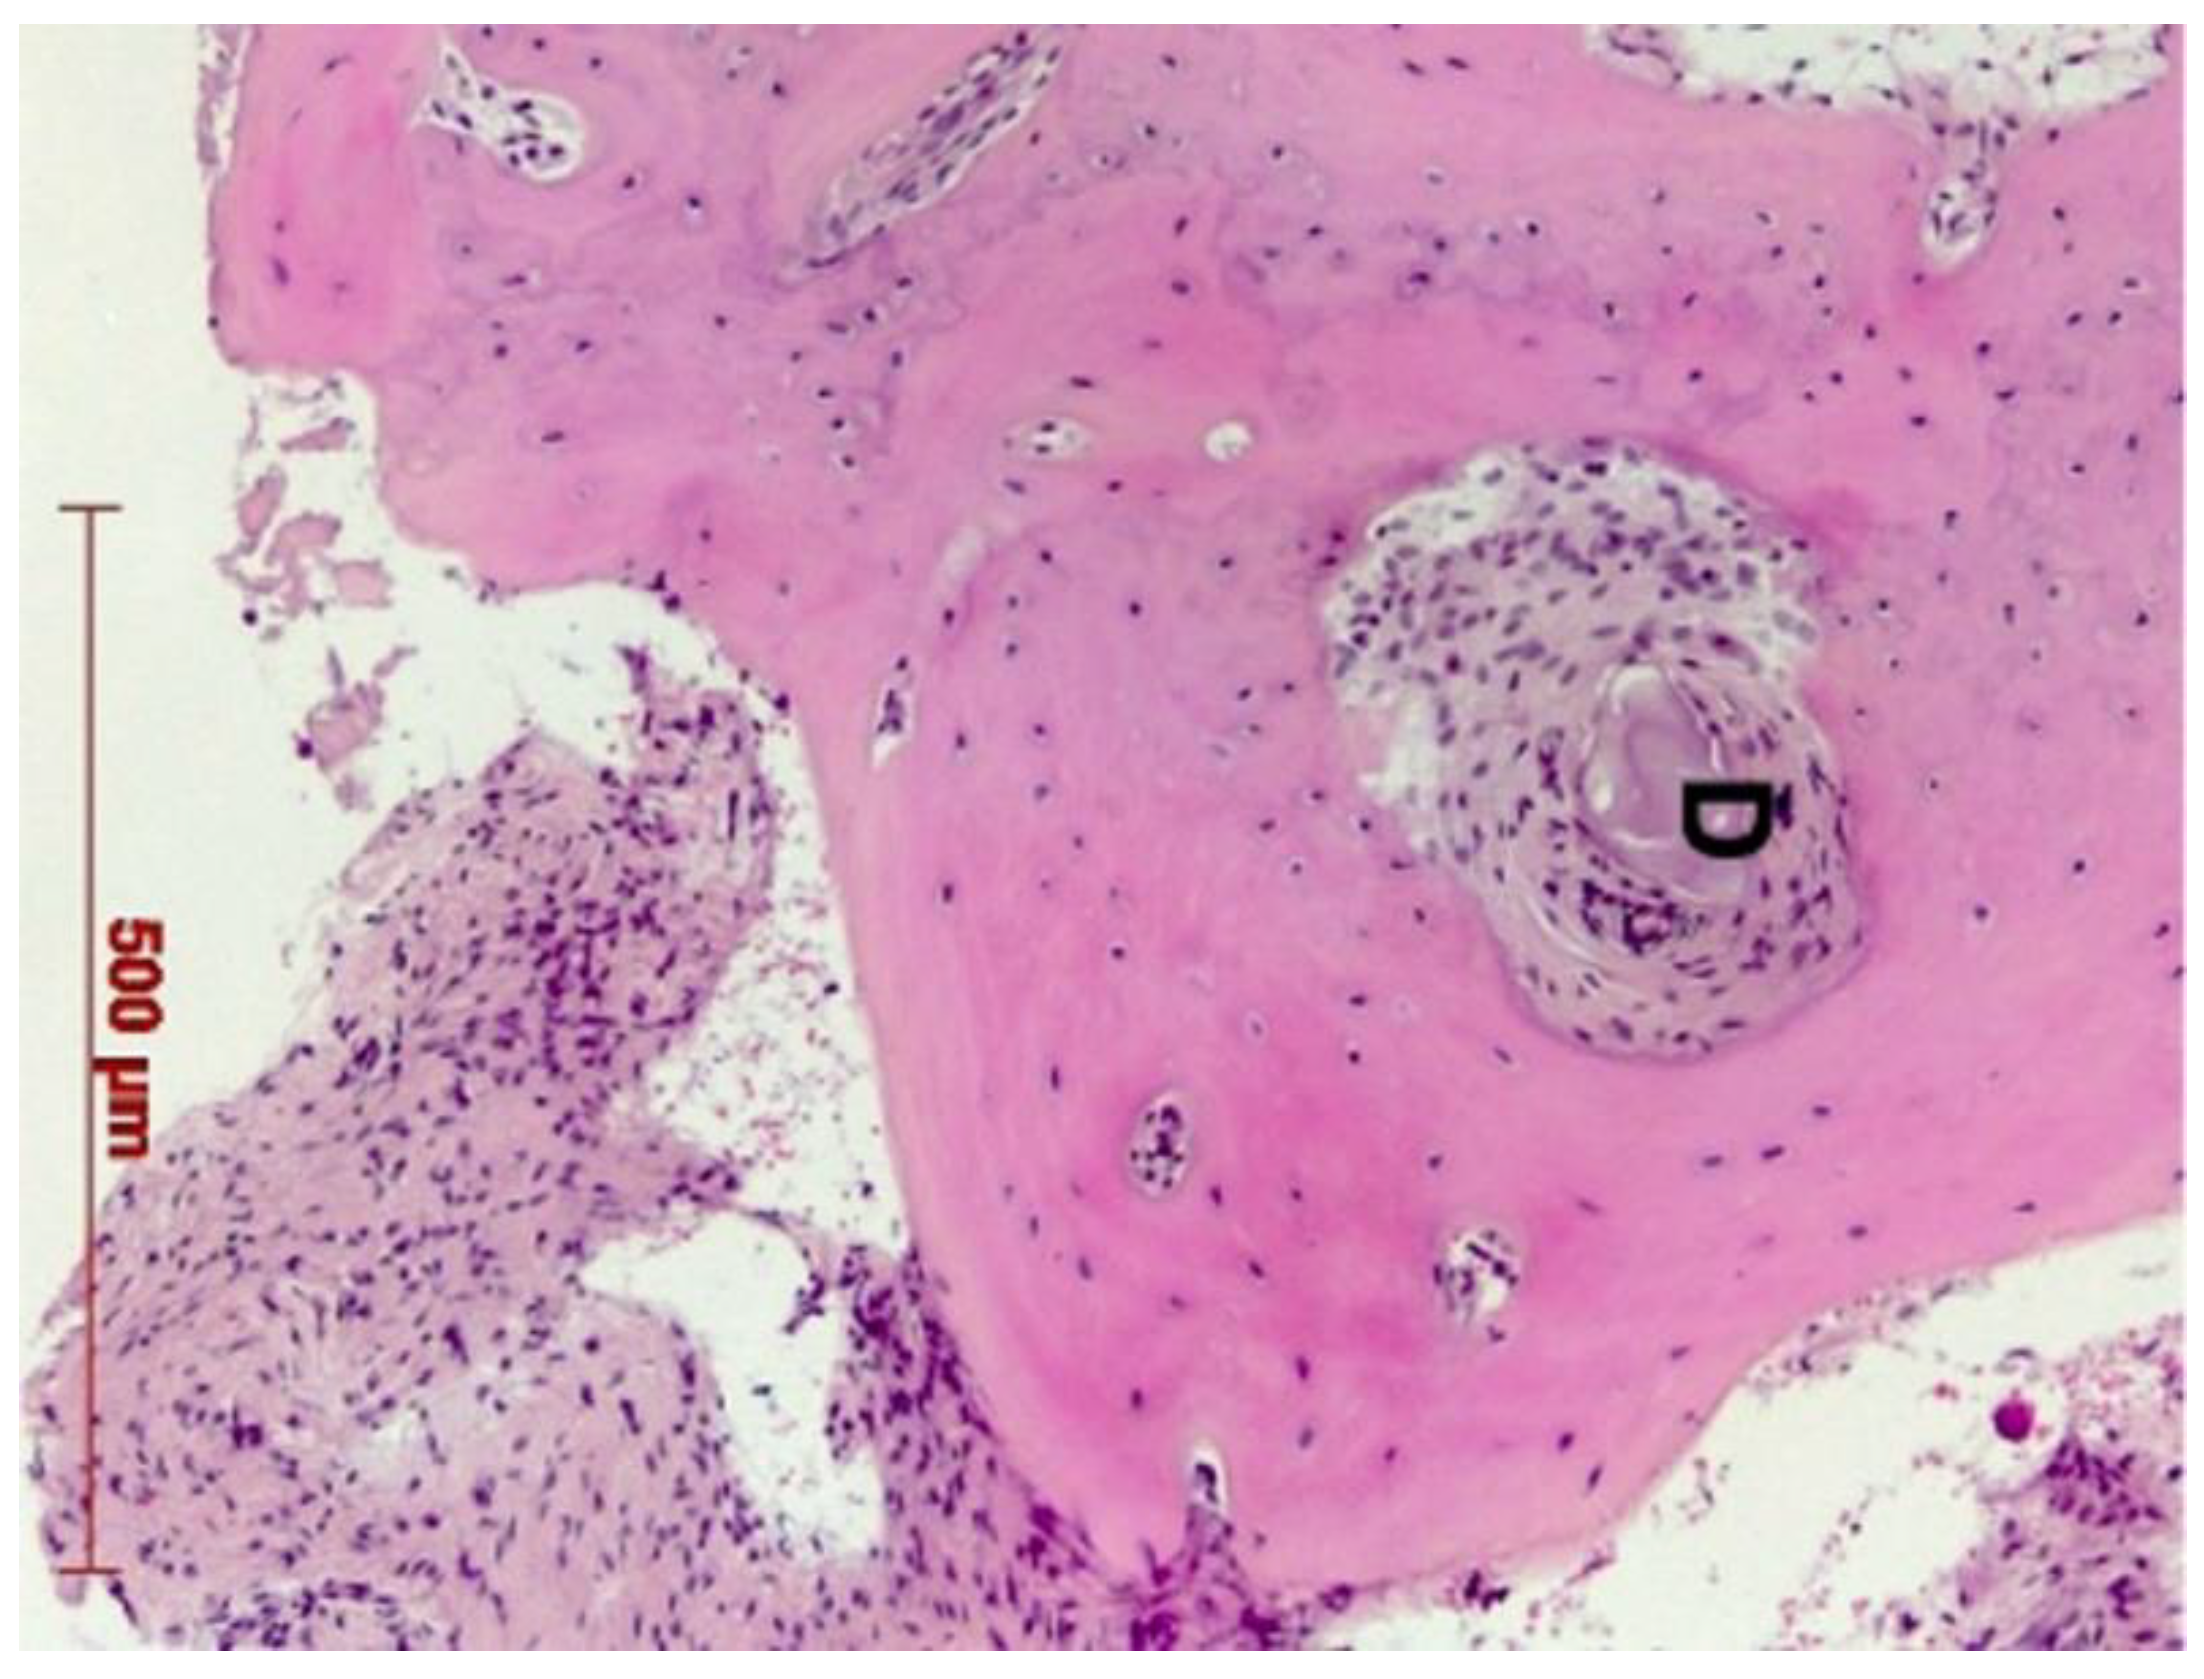

Histological Analysis

3. Results

3.1. Bone Quality